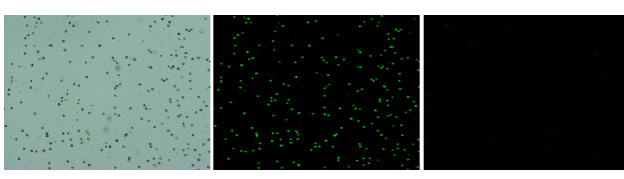

人膽管癌樣本,活性90.45%,結團率7.2%

Tips: 肝實質細胞經過解離后因為缺氧非常容易發(fā)生凋亡,導致占比很低,如果老師關注肝實質細胞的話,建議采用單細胞核懸液的方法。